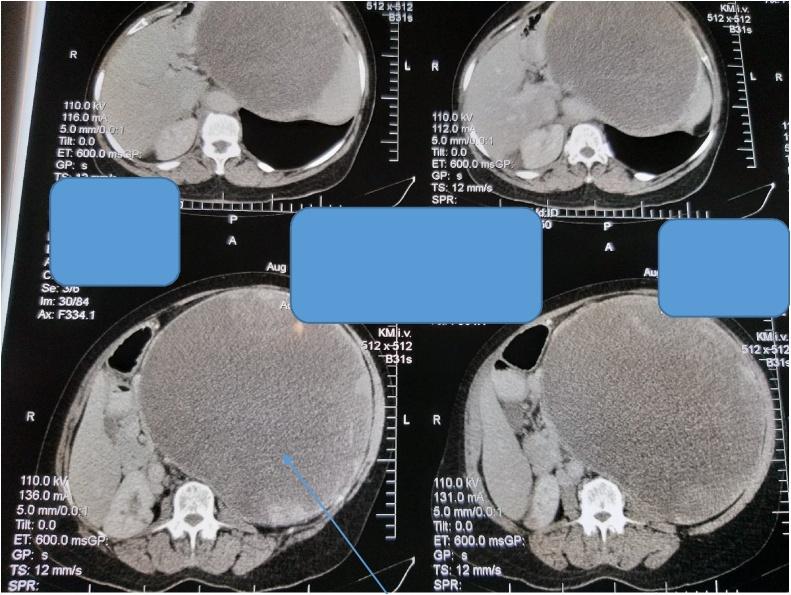

Two female patients aged 22 years and 65 years respectively, and an 11-year-old boy presented with giant pancreatic pseudocysts (>10 cm in diameter each) to our unit and were successfully managed. They all underwent exploratory laparotomy and cysto-gastrostomy with good outcome.

两名分别为22岁和65岁的女性患者以及一名11岁男孩因胰腺巨大假性囊肿(直径均>10 cm)前来我院就诊,并成功接受治疗。他们均接受了剖腹探查术和囊肿胃吻合术,效果良好。